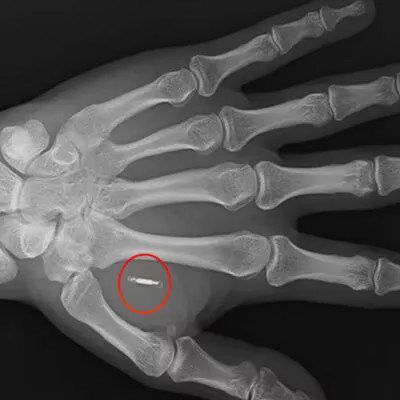

O debate é aberto e há muitas questões em torno desse meio inovador de pagamento. O sistema usa a tecnologia NFC (Near-Field Communication) com chips subdérmicos que servem para pagar contas como se fossem um cartão de débito ou crédito , mas incorporados ao corpo.

O tamanho do chip é o de um grão de arroz e é composto por um pequeno microchip e uma antena revestida com um biopolímero, um material de origem natural, semelhante ao plástico. Em relação à duração do chip, a empresa afirmou que seriam 8 anos na Europa e 3 anos nos Estados Unidos.

A tecnologia na qual se baseia foi desenvolvida na década de 90 e tem sido usada em chips de animais há muito tempo, mas a empresa britânica-polonesa especializada em simbiose de máquinas humanas Walletmor é a primeira a comercializá-la em humanos em grande escala para "substituir a carteira volumosa por um implante totalmente seguro". No momento, eles realizaram mais de 500 implantes apenas no Reino Unido e dizem que recebem consultas diárias.

A tecnologia utilizada pela Walletmor é NFC (Near-Field Communication), o sistema de pagamento sem contato que já está funcionando em todos os smartphones. O chip pode começar a funcionar imediatamente após ser implantado e eles prometem que ele sempre permanece no local onde é colocado.